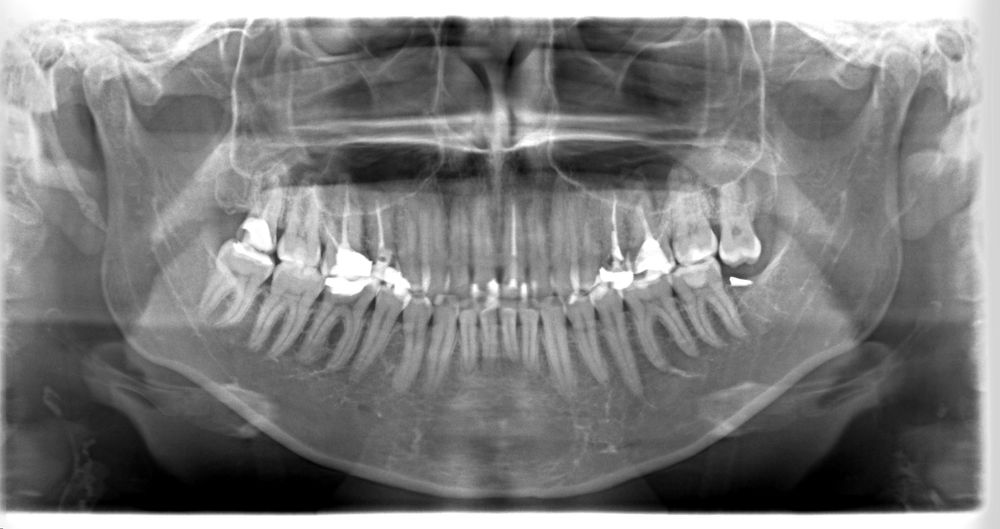

Взрослые зубные проблемыДобрый день. Мучаюсь с зубной болью 2недели, болит то один, то другой зуб, то сверху то внизу нет точной локальности. Болит приступами два раза в час по 10-15мин. Сил терпеть уже нет. Два врача подозревают невролгию. Т.к. сделали панорамный снимок, по нему всё хорошо. Либо вскрывать каждый зуб. Кто с подобным сталкивался. Как диагностируют, вылечились ли Вы если это в самом деле невралгия?

А с пазухой все хорошо, у лора были? На панорамном снимке не всегда удается рассмотреть проблемы с зубами, лучше сделать КТ. А при приеме пищи, от холодного, горячего боль усиливается? По ночам боли есть? Если есть возможность, прикрепите панораму, посмотрю

Anis, добрый день. У Лора не была, уши не беспокоят. На холодное горячее не реагирую. По ночам боль есть если проснусь сама попить, или в туалет(а от зубной боли не просыпалась) Была проблема с зубом 6ка с левой стороны наверху, по снимку видно что нерв удалили и канал не до конца запломбировали, и образовалась полость с гноем, зуб не болел, но появился свищ на десне этой 6ки, как врач обьяснил гной так просачивался с канала. Мы его не трогали т.к. не беспокоил и я то беременна то на гв была. Теперь свищ не беспокоит. но болит челюсть с правой стороны начиная от 2ки и до зубов мудрости. Боль сильная, при приступе уходит наверх к вискам. От этого болит голова и шея в затылочной области. КТ ещё не делала, врачи предлагают вскрыть 2ку и 6ку пока что.

Да, несколько зубов, которые теоретически могут беспокоить. А если уже была обнаружена киста на шестерке, то этот вопрос нужно срочно решать. Даже если свища нет, киста никуда не делась, это скорей всего и беспокоит. Гной в голове- это вам не шутки. Чревато серьезными осложнениями. Если удасться- перелечить каналы, если нет-удалять. По снимку сложно делать прогнозы.